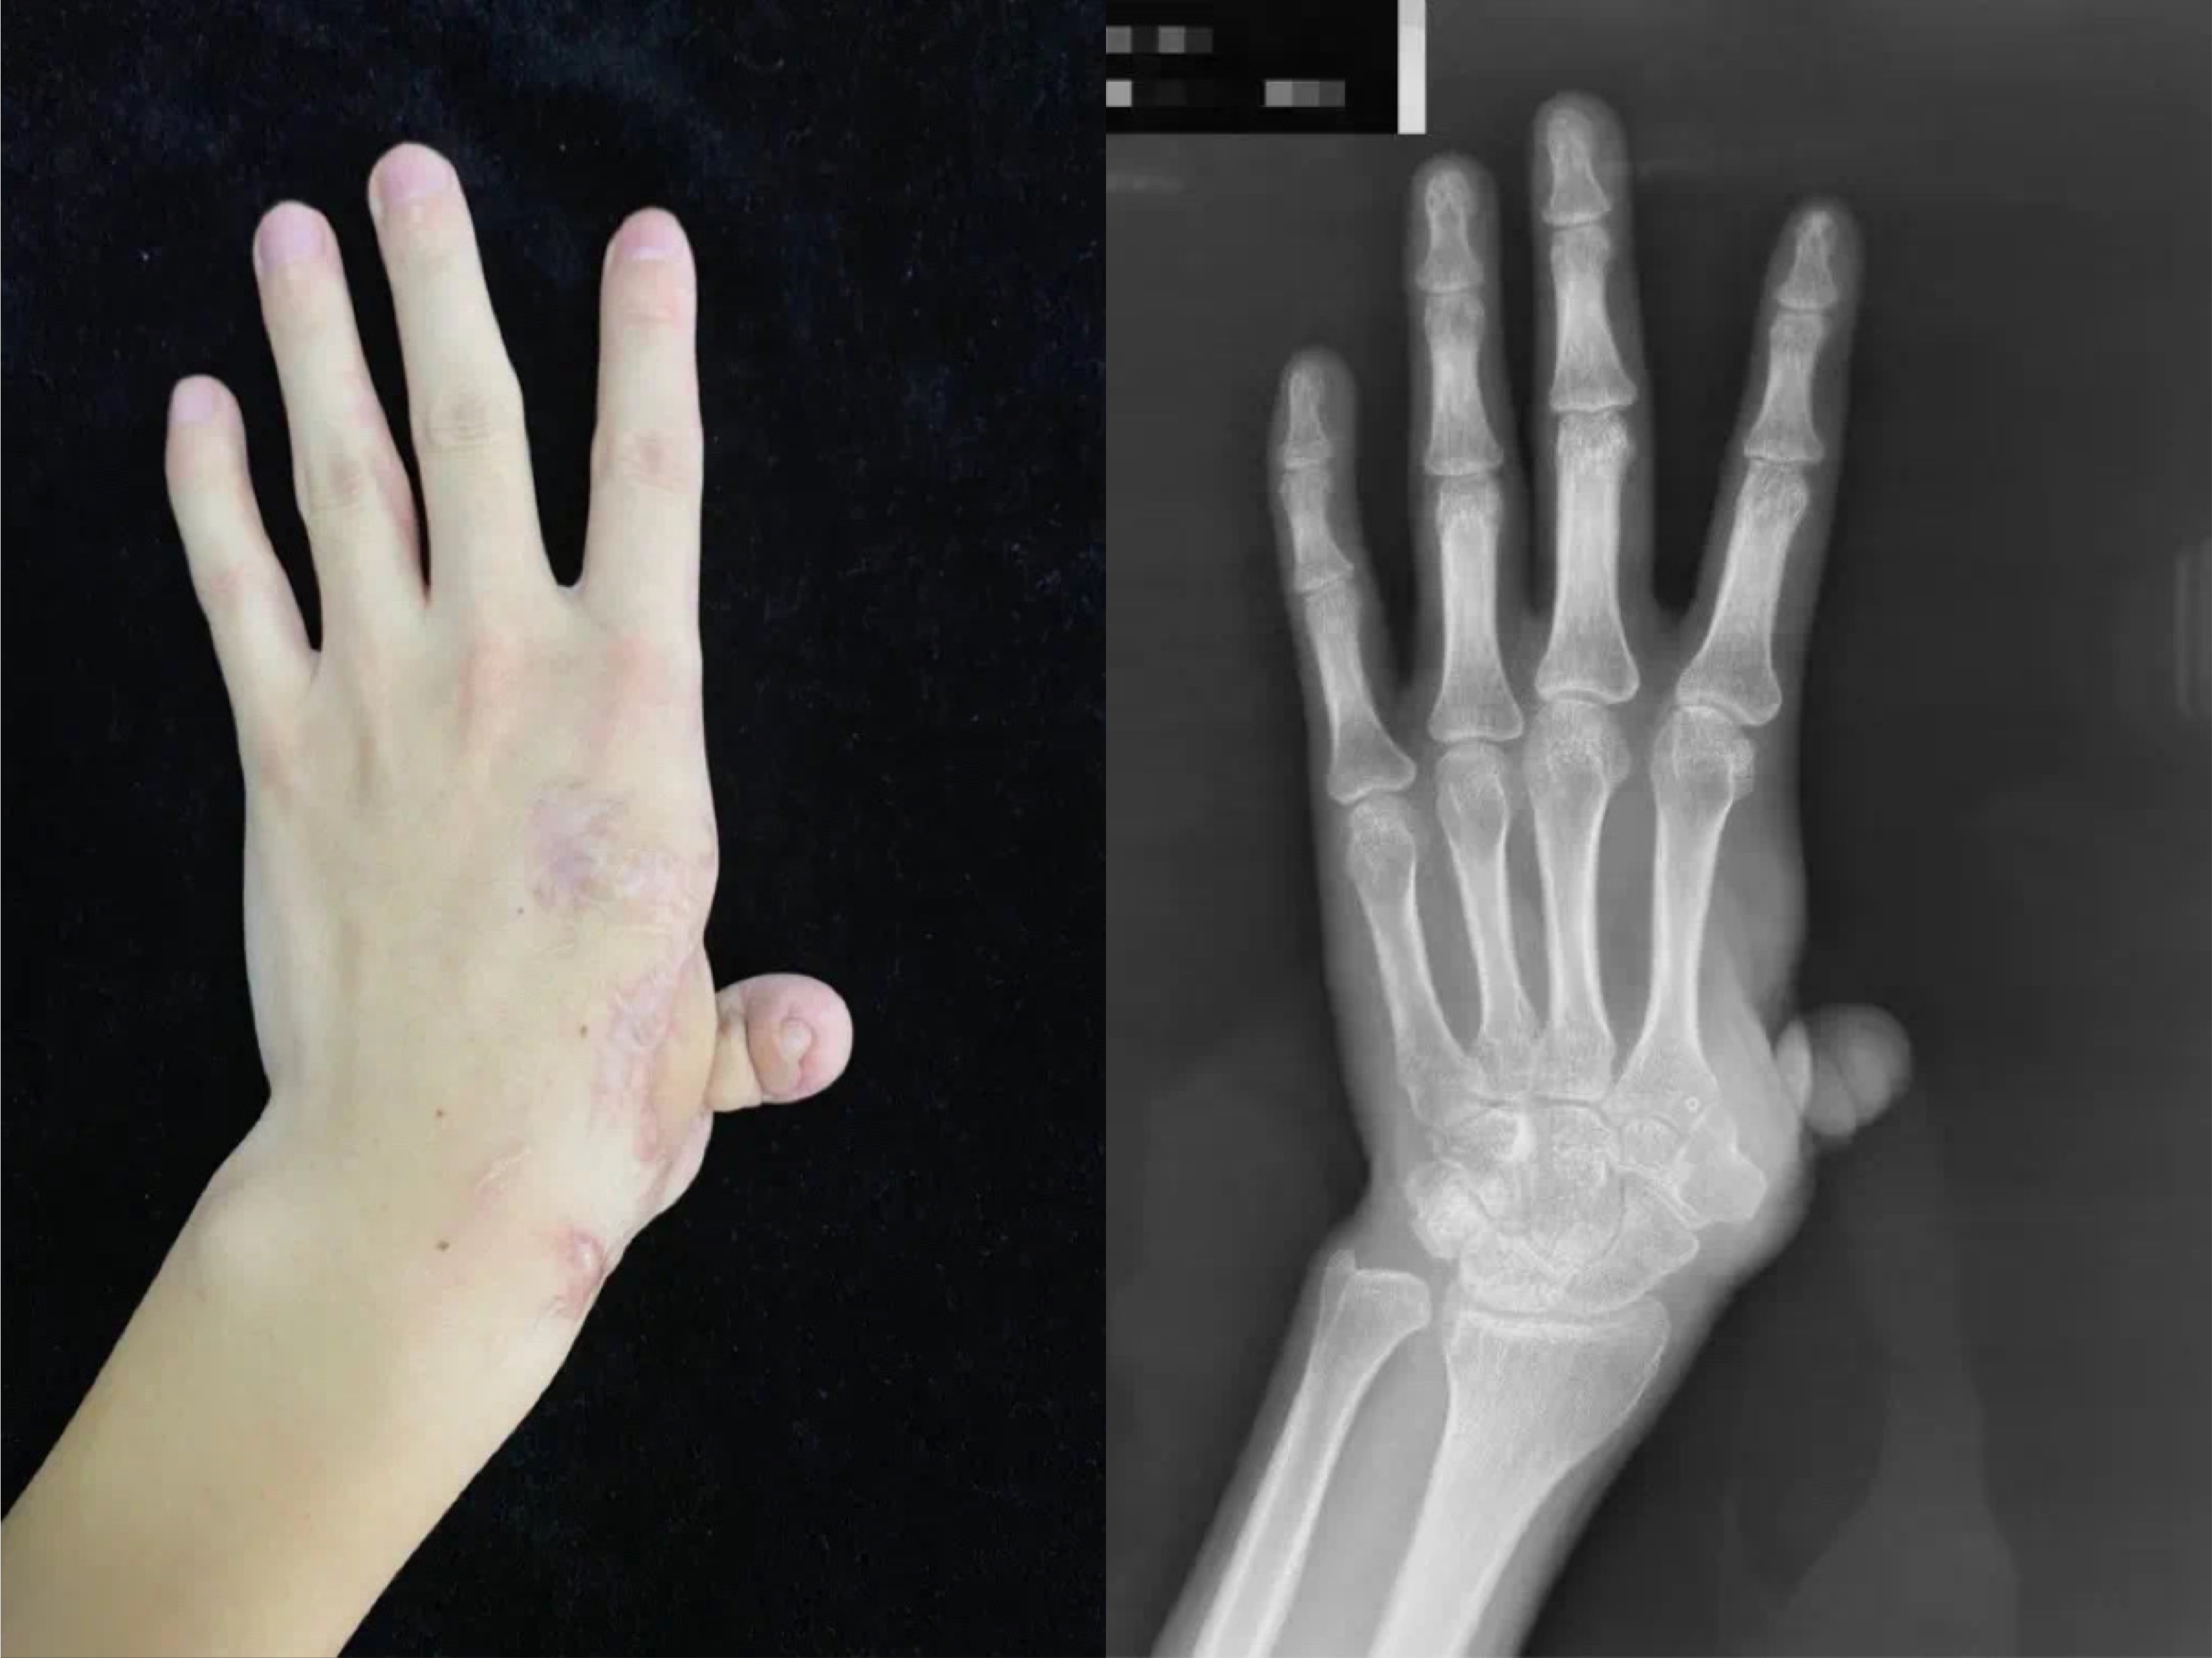

近日,该院专家团队为患者顺利完成了假体置入,腕掌关节韧带重建,游离穿支嵌合皮瓣移植等复杂精细手术。手术过程非常顺利,术中影像显示,假体位置满意,腕掌关节稳定且具备一定的活动度。再造拇指外观满意,长度合适,各皮瓣存活良好。

图为术后患者手部影像。(北京积水潭医院供图)

陈山林说,对于外伤后拇指缺损的患者来说,重建拇指是非常有必要的,拇指功能对于手功能的完整性非常重要。常规的拇指再造不论哪种重建方式,大多无法使患者获得具有活动能力的腕掌关节。而通过定制化的假体制作,即使形状不规则的腕掌关节,也可以达到完美的解剖学重建,使其能够活动。